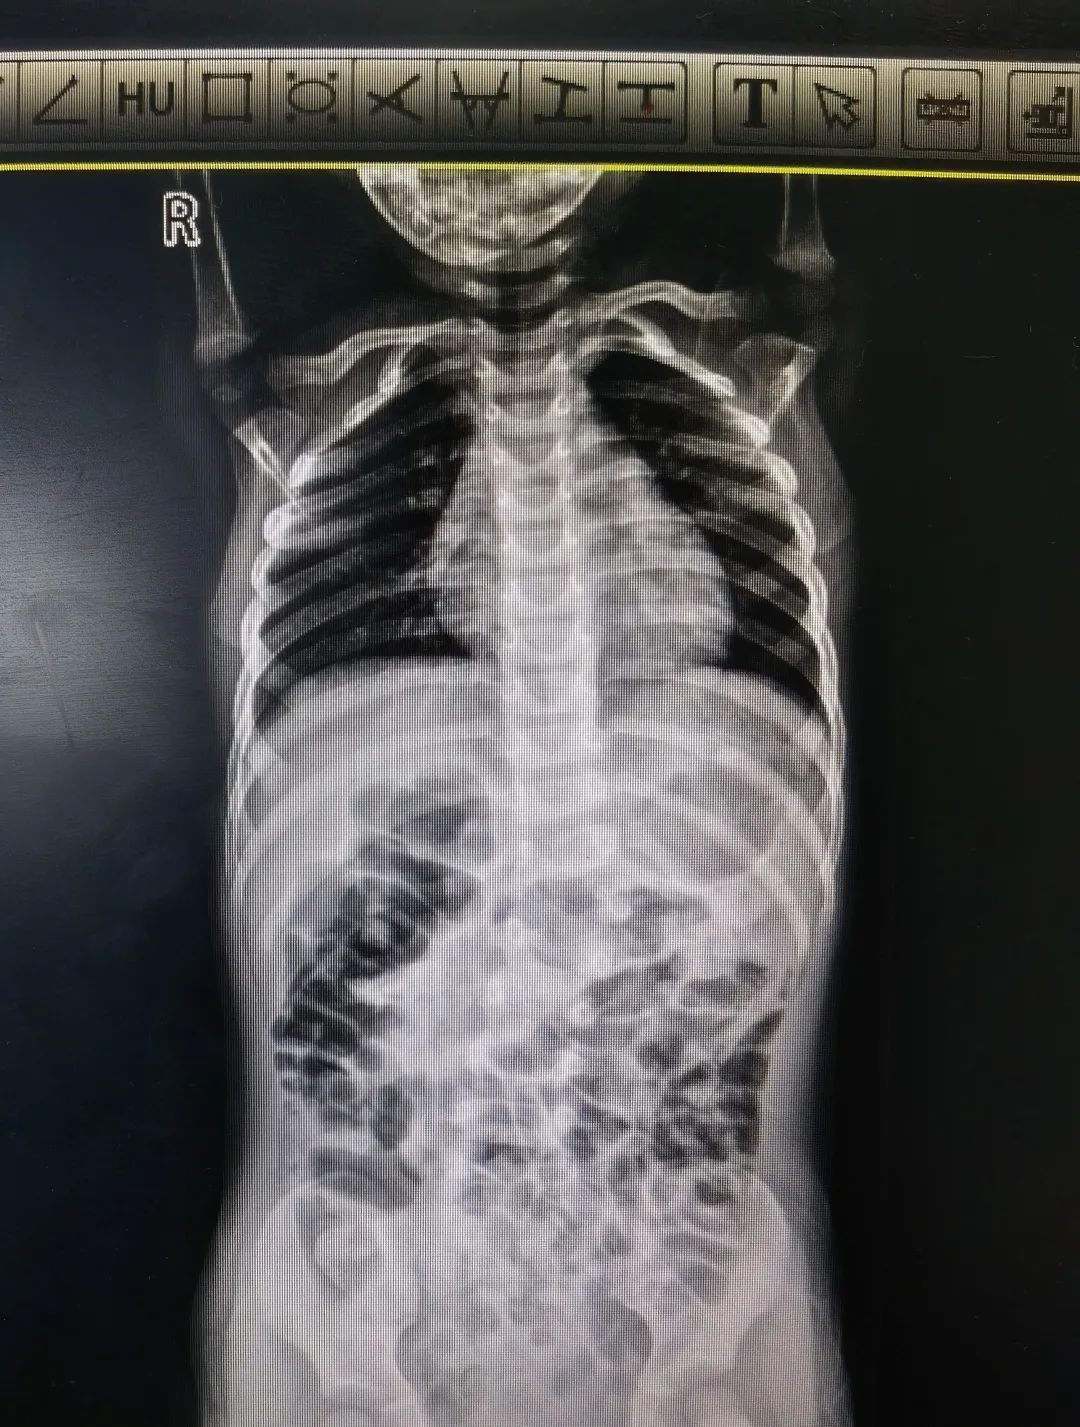

马凡综合征引起的脊柱侧弯术前术后图

“马凡综合征是一种常染色体显性遗传性结缔组织病,具有家族集聚性,可影响全身的结缔组织,有些孩子会出现脊柱侧弯的情况。”

陈文昊副主任表示,由于马凡综合征患儿骨骼发育异常,给手术增加了一定难度,但手术结果很不错的,达到了预期效果。他还指出一个自测马凡综合征的小妙招,让孩子把大拇指包住握拳,如果大拇指不能完全被包住,露出前面关节,家长就要当心了,建议去医院做进一步检查。